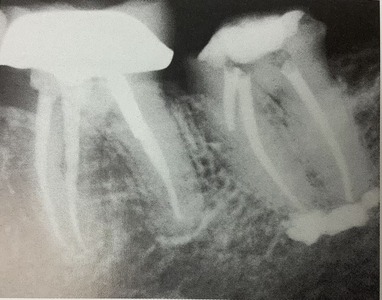

白い材料が

直ぐ下にあるアゴの神経の管近くにまで、

はみ出ています。